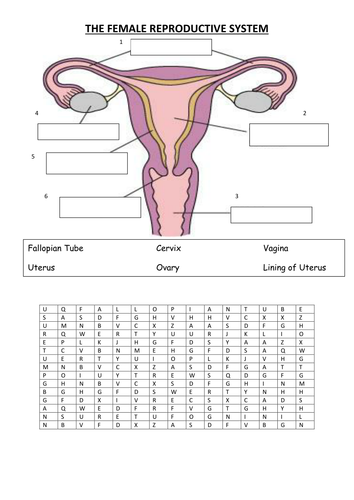

Pin By AGC On Worksheets Female Reproductive System Reproductive – If you are wondering what Anatomy Worksheets are and exactly how to use them to remember the body in a brief period of time, after that you have actually concerned the right place. In this write-up, you’ll discover what Anatomy Worksheets are, how to utilize them to discover the body components, as well as how to discover Female Reproductive Anatomy Worksheet.

Female Reproductive Anatomy Worksheet

Female Reproductive Anatomy Worksheet

For a enjoyable means to reinforce learning more about the body, you can utilize Female Reproductive Anatomy Worksheet. These resources are offered in a variety of formats, including image documents, Google Slides, and also PNG images. Some of them have tags to make it easy to determine parts of the body. Others consist of pictures of animals and other remarkable realities.

Some of the body worksheets are readily available for homeschooling. You can use them to teach kids the names of all the body organs, and also their appropriate placement. There are likewise vocab lessons and writing sentences to aid your kids exercise the brand-new details. You can also make use of these worksheets for science lessons.

The worksheet includes various body systems, such as the skeletal system, the muscles, as well as the brain. There are also tracing documents that children can utilize to trace as well as reduce out parts of the human body.